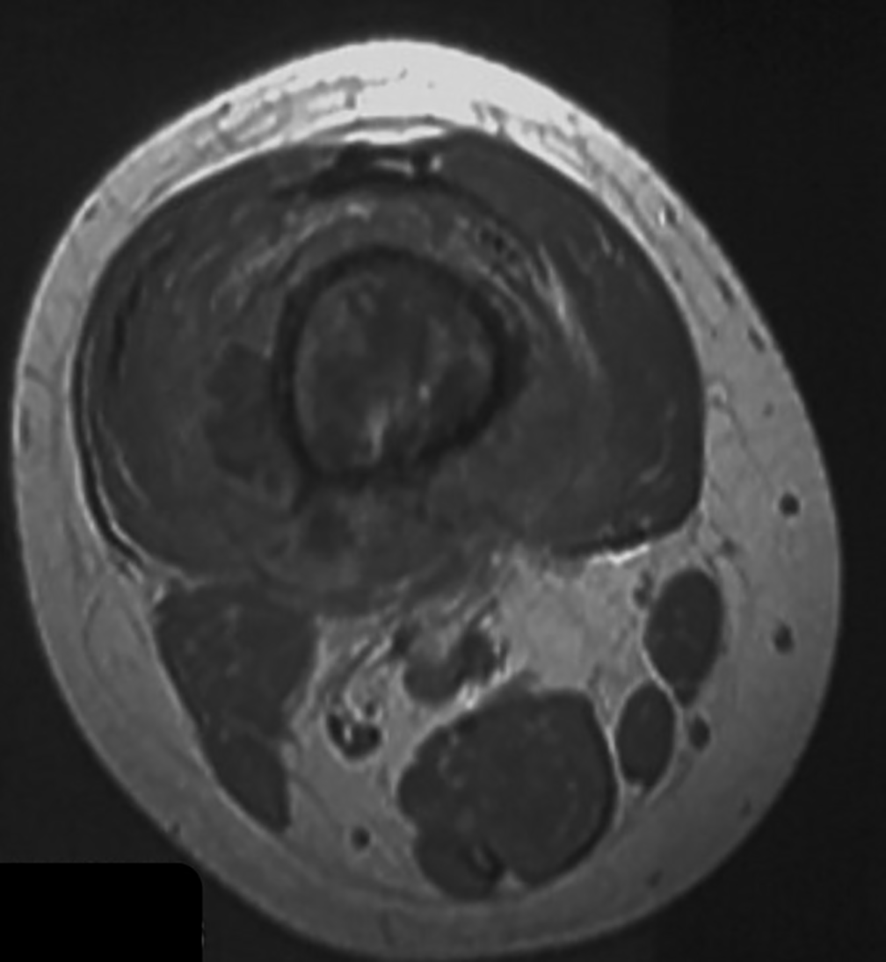

Figure 2

(A) Pre- and (B, C) post-chemotherapy T1-weighted cross-section MR images of a distal femur. The double directional arrow pointing towards the midpoint of the medullary cavity represents the width of fat layer.

3.3 Presence of fat layer after chemotherapy

Fat tissue has short T1 times and shows bright signal intensity. The maximum diameter of the fat layer on transverse T1-weighted sequences was measured as its width. The average width of the fat layer emerging after neoadjuvant chemotherapy was 0.39 cm (range: 0.06 to 0.64 cm) (Figures 2–4). The best threshold values for the fat layer were confirmed using ROC curves (Figure 5). The area under the curve (AUC) was between 0.5 and 1.0. The AUC for the fat layer predicting necrosis was 0.759 (CI: 54.4%–97.5%). Furthermore, at a threshold value of 0.32 cm, the sensitivity and specificity for predicting tumor necrosis were 0.882 and 0.455, respectively. Using logistic regression analysis, the significance of the fat layer as a histological indicator of necrosis was 0.03. Moreover, an increase in fat layer width was associated with a favorable prognosis (p = 0.011; OR = 0.000; CI: 0.000–0.117).

All patients underwent MRI after three cycles of neoadjuvant chemotherapy. The tumor length was measured by coronal T1-weighted sequences. Edema length was measured using coronal T2-weighted sequences with fat suppression. The fat layer surrounding the tumor in the MRI was defined as the fat signal observed after chemotherapy. Two clinicians browsed every layer of the T1 images and selected the image with the maximum fat width. The image was confirmed when clinicians chose the same one. We measured the maximum fat width on transverse T1-weighted sequences.